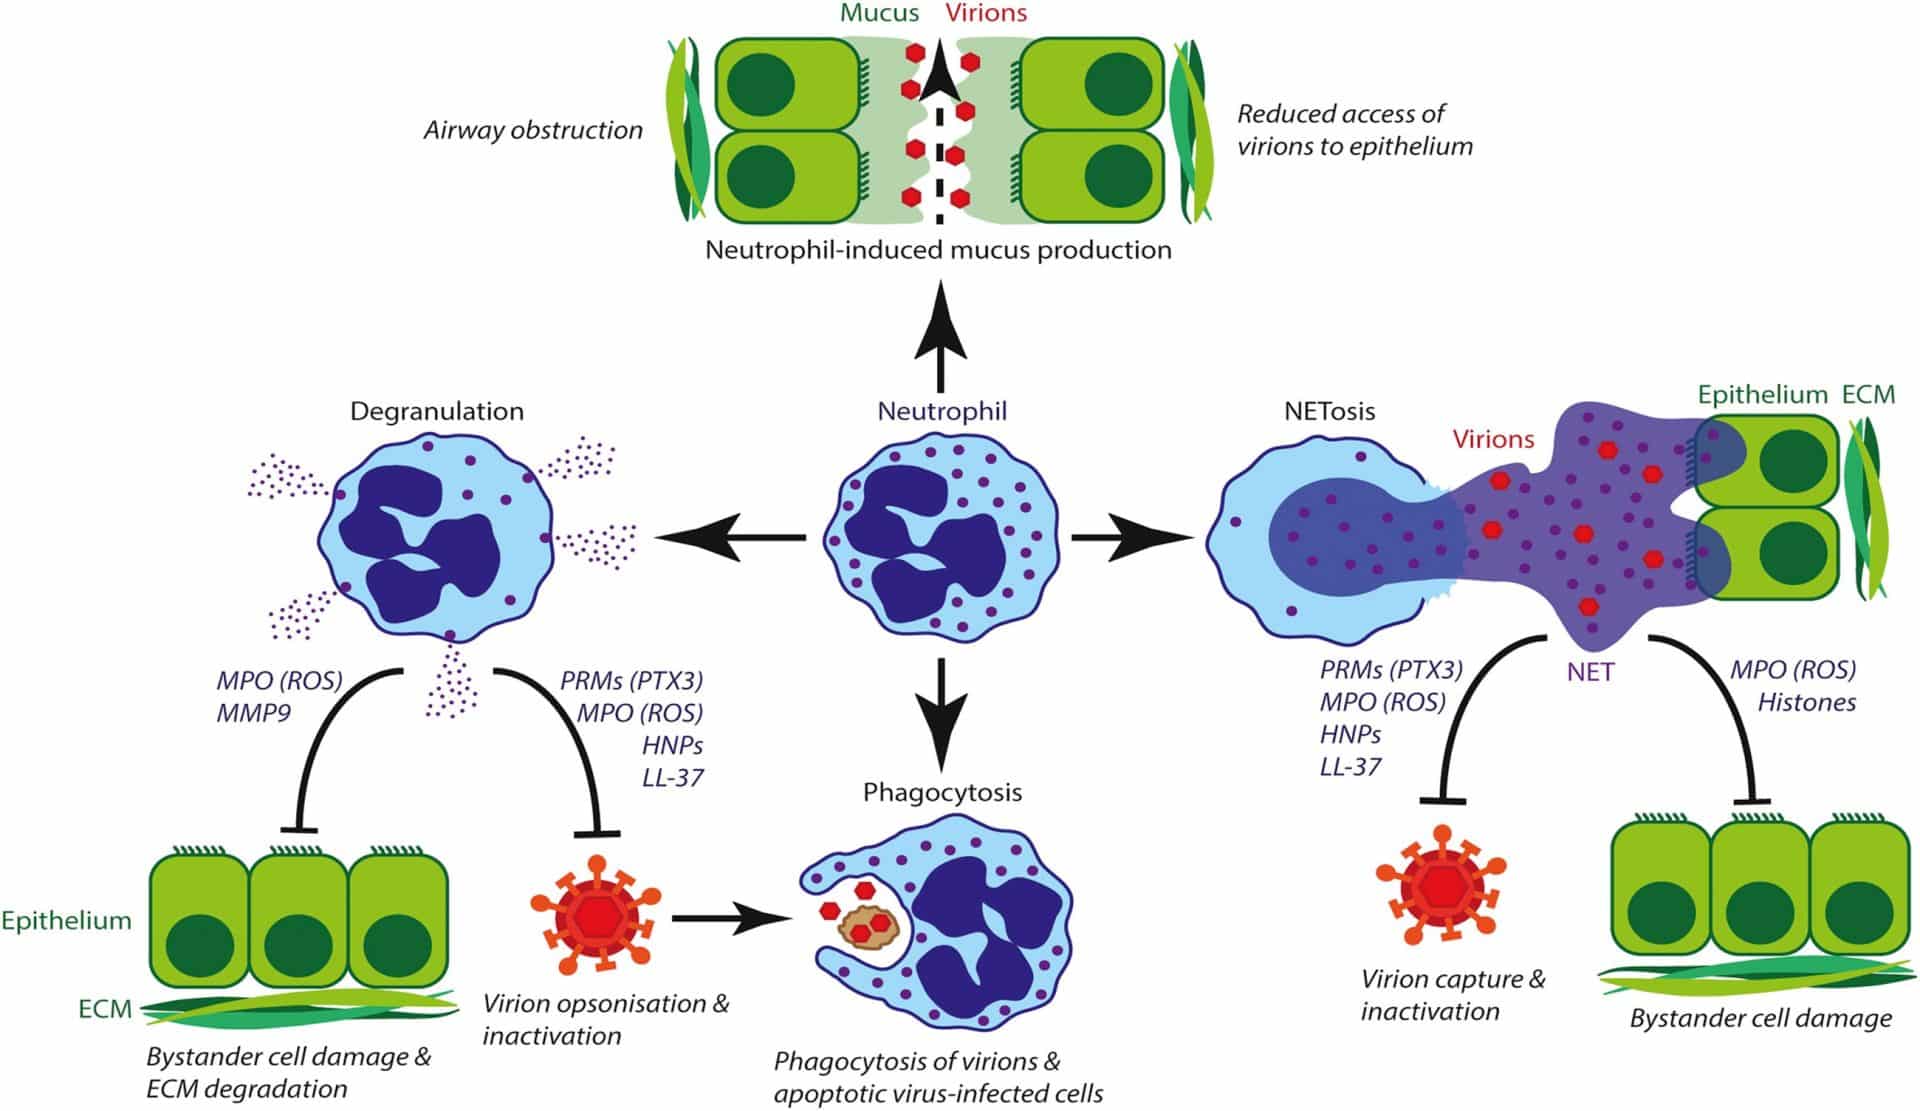

Role of neutrophils in the respiratory tract viral infection

The virus quickly spreads throughout the respiratory tract after being inoculated into the nasopharyngeal or conjunctival mucosa. Neutrophil-induced mucus production limits access of viral particles to the epithelium but obstructs airflow by plugging by mucus, cellular waste, and DNA.

Phagocytosis of viral particles and virus-infected cells limits viral spread. Neutrophil extracellular traps capture and deactivate viral particles and damage healthy cells. When the viral cytotoxicity and the host’s cytotoxic response combine to cause the necrosis of respiratory epithelial cells, the host’s inflammatory immune reaction is triggered, including both humoral and cytotoxic T-cell activation.